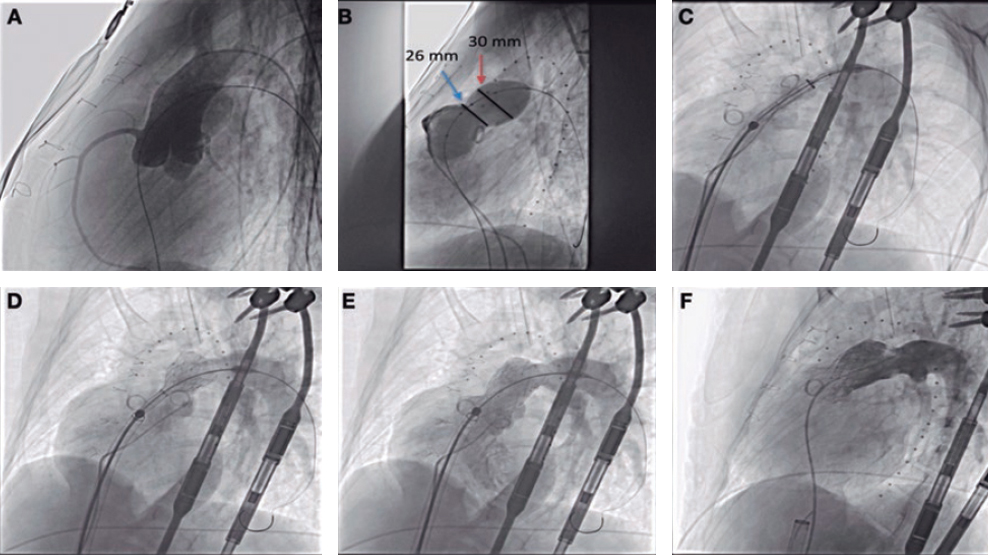

A 48-year-old woman with congenital pulmonary stenosis who required surgical valvuloplasty in 1978 presented with progressive dyspnea. The cardiovascular magnetic resonance imaging performed confirmed the presence of dilated right ventricle, severe regurgitation, and pulmonary artery aneurysm (39 × 25 mm). The heart team decided to perform a transcatheter pulmonary valve implantation. During pre-stenting with an uncovered 15-25 mm × 47-55 mm CP Stent (NuMED, United States) mounted on a 25 mm balloon of the native right ventricular outflow tract, stent embolization with spontaneous anchoring to the left pulmonary artery occurred (video 1 of the supplementary data, and figure 1A). Since the patient remained stable, a wait-and-see approach was decided to facilitate stent endothelialization. The stent (figure 1B) was used as the anchoring substrate 2 months apart of the proximal implantation for 2 longer Andrastent XXL 57 mm-stents (Andramed, Germany) on a 30 × 40 mm XL AndraBalloon to create a landing zone for the 29 mm Sapien-3 valve. The rest of the procedure was successful (figure 1C). The patient remained asymptomatic, with no perfusion defects as confirmed by the ventilation/perfusion lung scan and a mean transvalvular gradient of 7 mmHg without any residual regurgitation at the 6-month follow-up (figure 1D).

Figure 1.

In cases of aneurysmal pulmonary trunk and dilated native/non-calcified right ventricular outflow tract, the high risk of stent or valve migration may be prevented by the “planned” implantation of a first stent of smaller dimensions in a pulmonary branch. Then, sequential proximal stents may be anchored to this landing zone, which facilitates the reconstruction of pulmonary trunk with low risk of flow compromise in the jailed pulmonary branch. Further studies to assess this scenario are warranted.